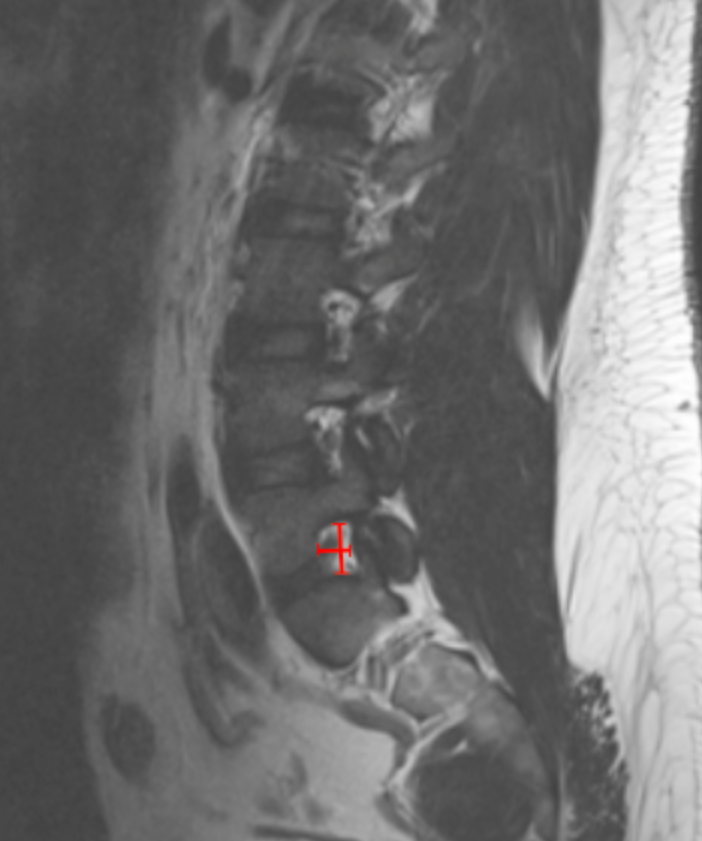

• On sagittal T2-weighted MRI, identify the disc level corresponding to the patient’s radicular symptoms.

• Select the parasagittal slice that best visualizes the neural foramen.

• Measure Foraminal Height:

• Identify the inferior cortex of the pedicle above and the superior cortex of the pedicle below.

• Measure the vertical distance (mm) between these two points.

• Measure Foraminal Width:

• On the same slice, identify the posterior vertebral body/disc margin (anterior boundary) and the anterior aspect of the superior articular facet (posterior boundary).

• Measure the anteroposterior distance (mm).

• Corroborate with axial T2 images to assess root compression or obliteration of perineural fat.